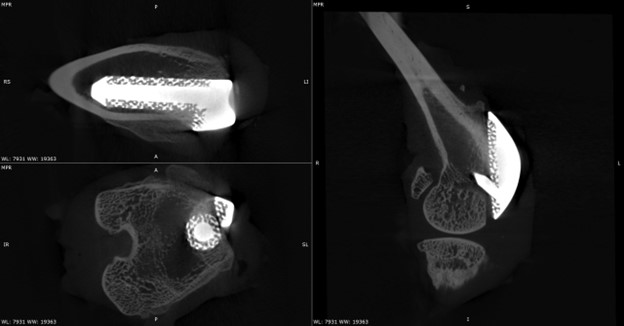

High‑resolution micro-CT enables the non‑destructive, 3D visualization of implants and surrounding bone over time. The images presented here showcase the use of micro-CT to study periprosthetic joint implantation and osseointegration in rabbit models, allowing tracking of implant positioning, bone remodeling, and early indicators of bone integration at multiple time points.

Below are micro-CT reconstructions of a femoral implant in a rabbit knee model. High-resolution imaging enables tracking of implant position and progressive changes at the implant-bone interface over time.

Temporal Assessment of Implant-Bone Interactions

Micro-CT imaging allows repeated scanning of the same implanted joint, providing a powerful means to observe temporal changes in bone architecture without disrupting the tissue. These scans allow monitoring of how the surrounding trabecular and cortical bone adapts to the presence of the implant, capturing subtle changes in bone volume, density, and structure as healing progresses. This approach enables precise comparison of early versus later stages of implant integration within the rabbit knee.